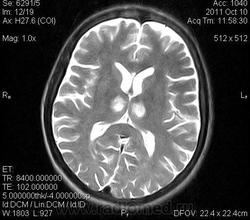

женщина 1963 года рождения. давность заболевания 10 дней.

Билатеральный таламический инфаркт. Либо венозный, либо вследствие закупорки одной из ветвей задней мозговой артерии - ЗМА (вариан развития ЗМА). Но не средней мозговой артерии (СМА). Мне представляеться, что здесь второе... За венозный инфаркт данных не вижу.

Может не как следствие закупорки сосуда, а гемодинамический инфаркт в ВББ (таламо-субталомических ветвей ЗМА)?

Может быть что угодно, но:

1. гемодинамические инфаркты встречаются нечасто.

2. должно предшествовать снижение МОС/АД

3. как правило, это инфаркты пограничных зон (смежного кровоснабжения), а не базальных ядер.

Я неприклонен... Инфаркт ЗМА (вероятно, варианта развития левой ЗМА - эмболии, мойа-мойа..).